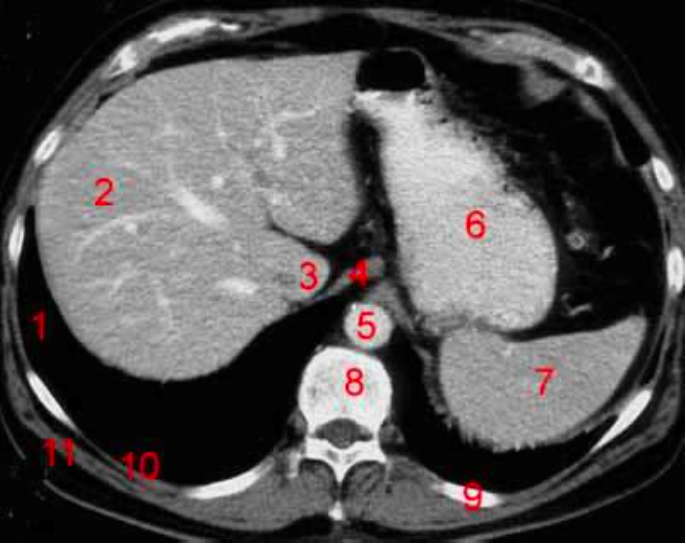

Number 1?

R kidney

Number 2?

Rt lobe of liver

Number 4?

Rt diaghragmatic crus

IVC

Rt lobe liver

R lung

Number 6?

Stomach

Number 5?

Rt ureter

Number 9?

Superior mesenteric artery

Number 8?

Bladder